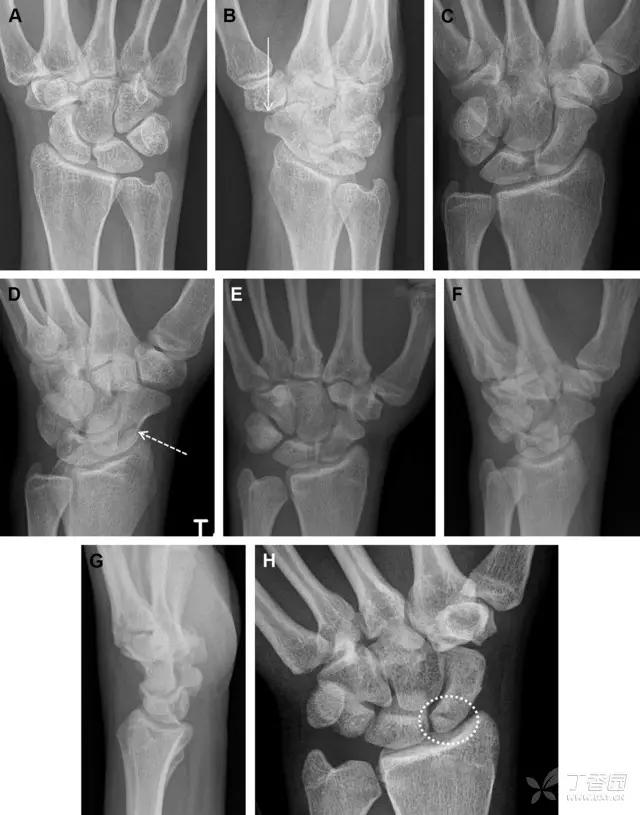

32 掌板骨折

掌板是掌指关节和指间关节关节囊掌侧的纤维结构,防止关节过伸。掌板的远端部是增厚的纤维软骨,附着于指骨掌侧基底部,而其两侧与侧副韧带的纤维融合。掌板骨折多发生于过伸损伤,为撕脱性骨折。

图 3 掌板骨折(A~C)小指前后位、斜位、侧位片,由于骨折的部位及特点,在前后位片上通常难以发现骨折;放大后的斜位(D)、侧位(E)可见一骨碎片(白色箭头)

33 腕掌关节骨折脱位腕掌关节骨折脱位为高能量损伤,常伴有神经损伤。腕掌关节组成骨多,侧位片上重叠遮挡多,骨折不易发现,容易漏诊。在前后位片上,关节面不平滑、关节间隙不对称、关节皮质破坏、关节面重叠常提示腕掌关节骨折脱位。特别是第 4、5 腕掌关节脱位,在前后位片上不容易发现;该损伤不稳定,也称为「变异型拳击手损伤/骨折」。

图 4 第 4、5 腕掌关节骨折脱位。(A)正常腕掌关节,关节面平衡起伏、平行;前后位(B)、斜位(C)、侧位(D),第 5 掌骨近端附近软组织肿胀(白色箭头),冠状面关节面重叠,背侧撞击剪切应力致钩状骨骨折(*),在前后位及斜位片上可见双密度影。第 4 掌骨底部可见微小骨折碎片(D,虚线箭头),第 4、5 掌骨掌侧成角。(E~G)变异型拳击手损伤:第 4、5 掌骨背侧脱位而未见骨折(E,虚线方框),钩状骨有骨折小碎片(F,短虚线箭头),第 4 掌骨基底部关节内骨折(G,长虚线箭头)

34 钩状骨骨折

钩状骨骨折可发生于体部和钩部,钩部骨折更多见,可合并有第 4、5 腕掌关节脱位。受伤机制由直接*力暴**或腕横韧带撕脱伤所致。骨折征象包括钩部无显示、骨皮质边缘模糊、硬化或双密度影等。常规的正侧位常无法明确诊断,需要加拍腕管位,可清晰显示其钩部。

图 5 打高尔夫球后腕部急性疼痛。常规腕关节 X 线片正常(X)。腕管位片(B)隐约可见钩部横行骨折(虚线箭头),CT 检查(C、D)进一步明确了诊断

35 三角骨骨折

三角骨骨折是除舟状骨骨折外腕关节常见的骨折之一。其背侧是背侧桡腕韧带的附着点,因此背侧骨折更常见。常规正侧位片基本可明确诊断。背侧骨折可在侧位片上看到一小骨块。

图 6 三角骨骨折。(A)前后位片骨折不明显,(B)仅在侧位片上见一小骨块(短箭头),伴有软组织肿胀(长箭头)。